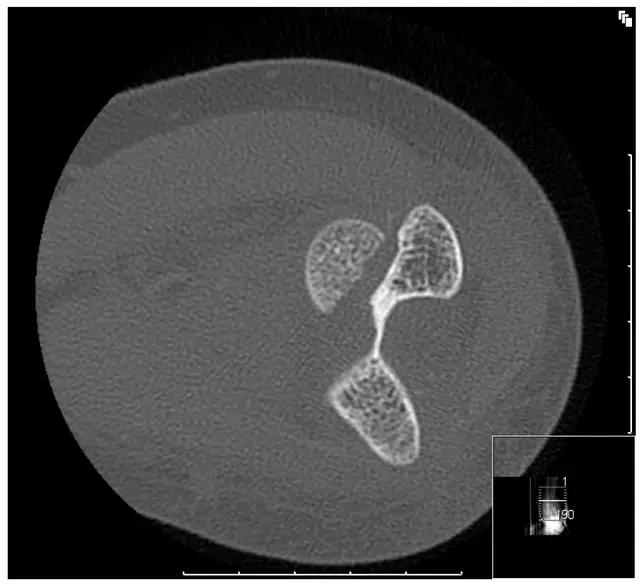

6. Jefferson 骨折

寰椎环的压缩性骨折,骨折是由枢椎压缩性外力引起,骨折多发生在寰椎前侧后侧以及侧方小关节。

第一颈椎双侧性前、后弓骨折,X 线片上很难发现骨折线,有时在正位片上看到 C1 关节突双侧性向外移位,侧位片上看到寰椎前后径增宽及椎前软组织肿胀阴影,CT 检查最为清楚,而 MRI 检查智能显示脊髓损伤情况。

A 图是稳定的 Jefferson 骨折(横韧带完整)轴位像。B 图是不稳定的 Jefferson 骨折(横韧带撕裂)轴位像